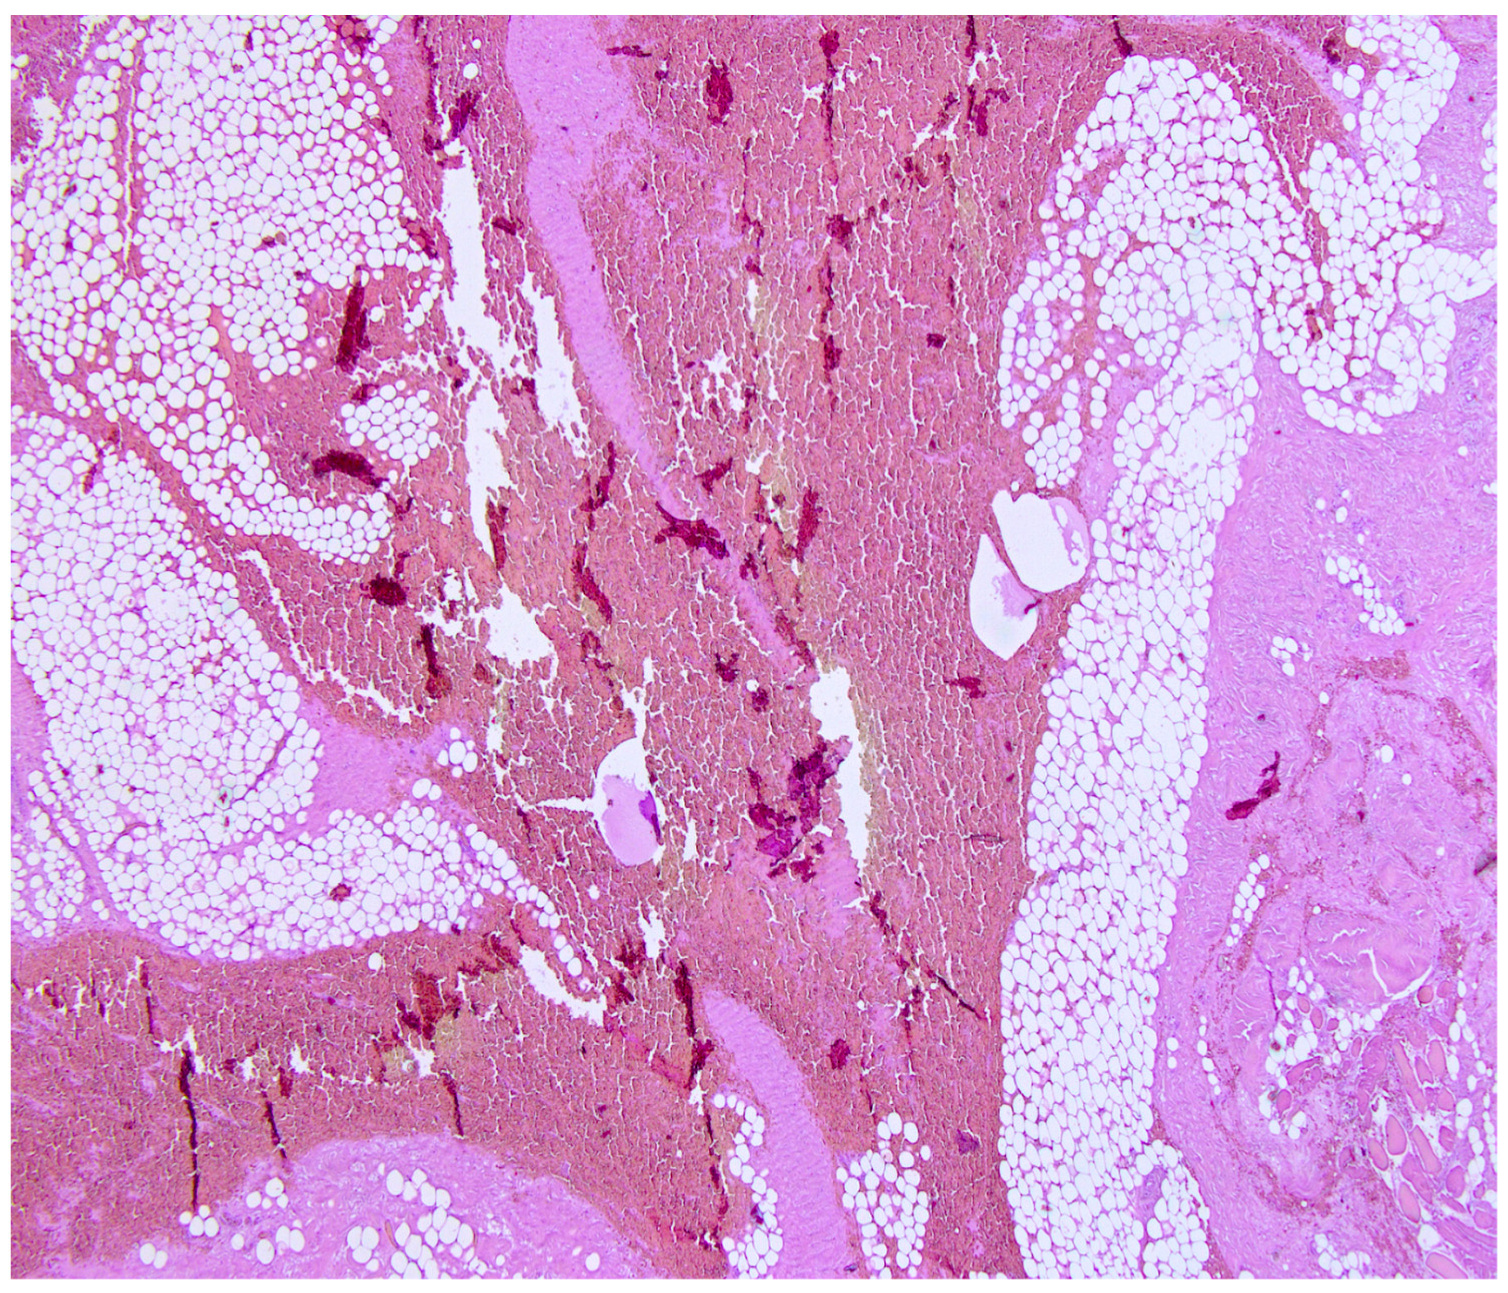

Impact of Cardiac Surgery Scar on Heart Rupture Following a Fall from Height

Napoletano, G.; Treves, B.; De Paola, L.; Del Duca, F.; Ghamlouch, A.; Frati, P.; Maiese, A. Impact of Cardiac Surgery Scar on Heart Rupture Following a Fall from Height. Diagnostics 2024, 14, 2472. https://doi.org/10.3390/diagnostics14222472